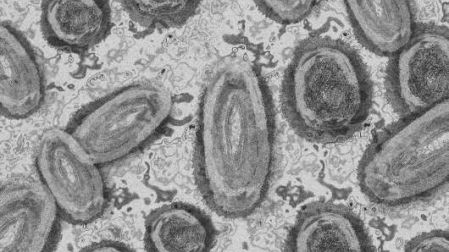

Alarmante predicción: Viruela del Mono va a mutar y variantes mortales podrían llegar a CDMX

La viruela del mono, o brote de mpox, fue declarada como emergencia sanitaria por la OMS; en redes circula una alarmante predicción.

De acuerdo con la OMS, esta vez los brotes no son consecuencia de la circulación de una misma variante del virus, sino de más de una. Además de que han observado niveles de riesgo y de contagio diferentes, puesto que hace dos años la transmisión era casi exclusivamente por vía sexual.